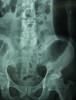

E de Paget